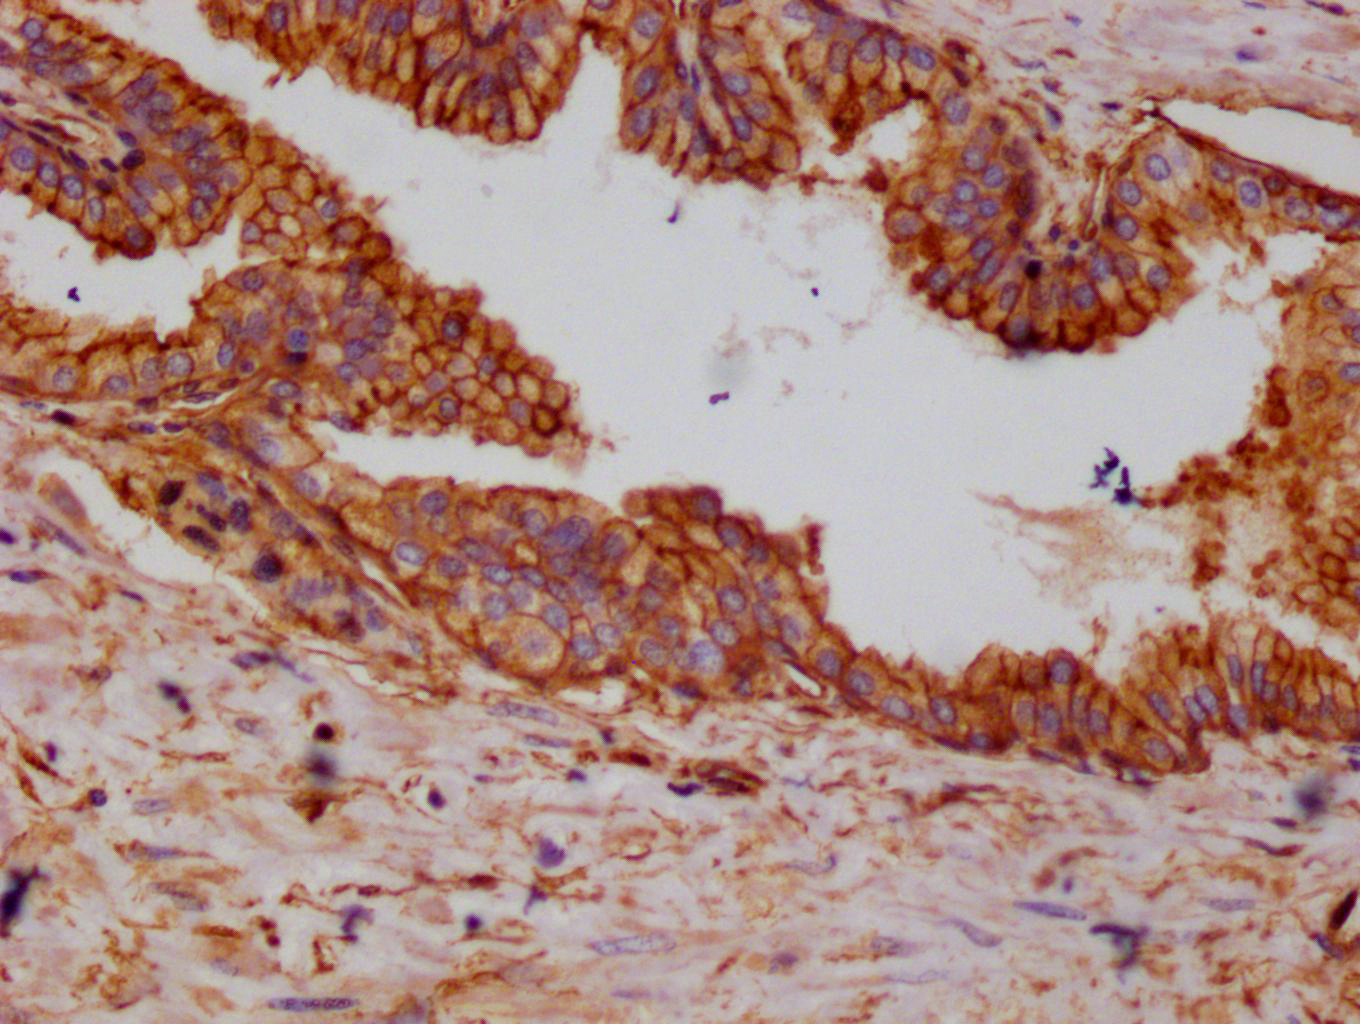

IHC image of CSB-RA987782A0HU diluted at 1:100 and staining in paraffin-embedded human prostate cancer performed on a Leica BondTM system. After dewaxing and hydration, antigen retrieval was mediated by high pressure in a citrate buffer (pH 6.0). Section was blocked with 10% normal goat serum 30min at RT. Then primary antibody (1% BSA) was incubated at 4°C overnight. The primary is detected by a Goat anti-rabbit polymer IgG labeled by HRP and visualized using 0.05% DAB.